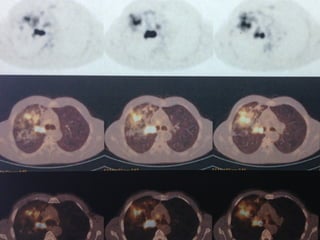

• PET –CT:

– Sağ ana bronş içine uzanan 35X18 mm kitle (SUDmax:13,0)

– Komşuluğunda 4R (SUDmax:3,7)

• PET –CT: – Sağ ana bronş içine uzanan 35X18 mm kitle (SUDmax:13,0) – Komşuluğunda 4R (SUDmax:3,7) – Sağ üst lob parankiminde yaygın fibrotik düzensizlik, kalınlaşma (SUDmax:7,3). – Pelvis kemiklerinde ve sağ 6.kotta fokal sklerotik lezyonlar, MR ile korelasyon